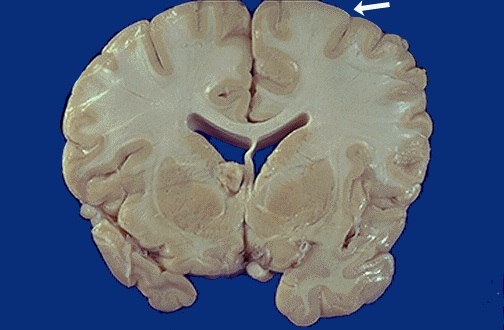

| This is tuberous sclerosis, an autosomal dominant condition characterized by mental retardation and seizures beginning early in life. The characteristic feature is the presence of "tubers" which are enlarged and firm, whitened gyri. A "tuber" is seen at the white arrow. [Image contributed by Jeannette J. Townsend, MD, University of Utah] |